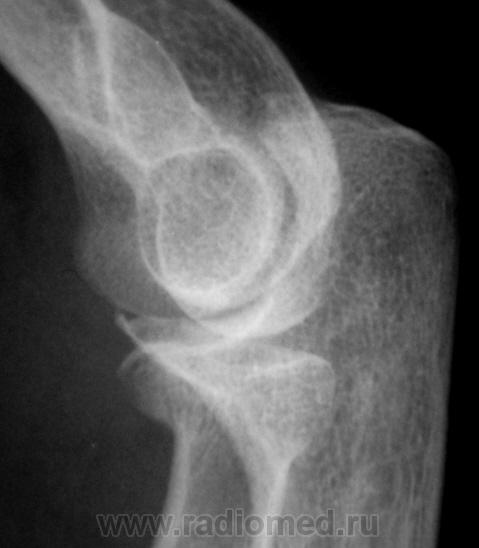

Травма. Пациент направлен на рентгенографию локтевого сустава.

перелом головки луча, встречается не так и часто.

Внутрисуставной,краевой перелом головки лучевой кости.